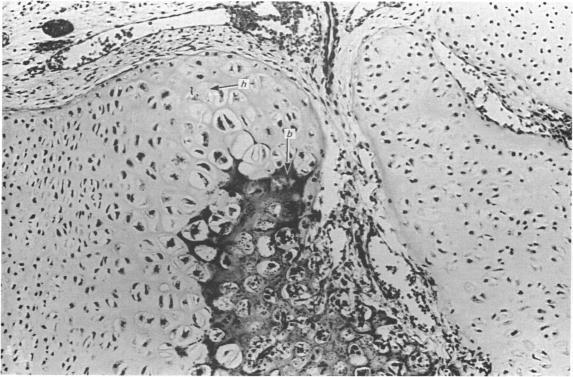

Bone formation in the vertebral centra commences within the centrum and is in this respect analogous to the secondary ossification which occurs in the epiphysis of a long bone. Bone tissue first appears at about the 85 mm C.R. stage and not in the 55 mm C.R. length embryo; at the latter stage blood vessels and calcification alone were observed. The connective tissue cells within the cartilage canal appear to assist osteogenesis by providing osteogenic cells which lay down bone in the walls of the cartilage canal, and provide cells which remove calcified cartilage found at the periphery of the canal; they assist growth by producing an appreciable number of chondrocytes that permit lateral expansion of the centra. Osteogenesis appears to occur in multiple foci within the growth plate of the older embryos and could account for the rapid rate of growth of vertebrae. Bone formation occurs in both mineralised and unmineralised matrix (as seen on the walls of the cartilage canals). The blood vessels within the growing vertebra tend to follow the zone of cartilage hypertrophy.